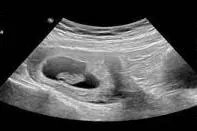

b超照片怀孕初期图片

的有关信息介绍如下:概述b超照片怀孕初期检查的内容包括子宫的大小和位置,宫腔内是否能看到孕囊和孕囊的大小,囊内是否能看到卵黄囊、胎芽和胎心,双侧附件是否有异常回声。一般怀孕40天左右看到卵黄囊是正常的。怀孕6周后,可以看到胎心和胎芽,就可以测量出胎芽的大小。方法在怀孕初期做超声检查时,子宫仍然位于盆腔内。通过腹部超声不能很好的观察到子宫内胚胎的发育情况,做超声检查需要孕妇憋足膀胱内的尿液后,再做腹部超声检查,怀孕12周以后,增大的子宫突出于盆腔,做超声检查时不再需要憋尿。

b超怀孕初期图片注意事项1、一般在怀孕后40天左右可以做b超。检查前需要憋尿,因为膀胱是满的,这样可以看到子宫腔和附件内的具体情况。2、尽量穿宽松的衣服,方便检查。3、随着胎儿的生长发育,子宫内也有一定量的羊水。怀孕10周后可以不空腹做b超。4、在怀孕的哪个阶段做b超,都有相应的检查项目,而且b超检查没有辐射,不会影响胎儿,所以不要错过,按时产检。